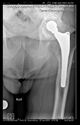

The direction of the cup stem was determined by the guide wire. The aiming device was needed to introduce this wire. After removing the aiming device, the next step was the drilling. Since a cannulated drill bit was used, the previously installed wire could guide the process. A self-positioning reaming tool was then used in the drilled channel. In the prepared cavity, the cup was fitted perfectly. Of the two stemmed cups available to us, the McMinn cup (Waldemar Link, Hamburg, Germany) had the simpler geometry and was therefore chosen. The stemmed cup was inserted according to the manufacturer’s recommendation. In the presence of a significant bone defect, a synthetic bone graft may be impacted for substitution.

The radiological examination allowed us to verify the close bone-to-implant contact and the unchanged position of the implant during follow-up.

In all the cases operated with the above-described targeting procedure, the stems of the cups remained between the cortical bone surfaces without perforation of the linea terminalis, as shown by postoperative radiographs. There were no complicated surgical situations. In 16 cases, the wound healings were uneventful, and the hips were able to bear weight again after postoperative rehabilitation.